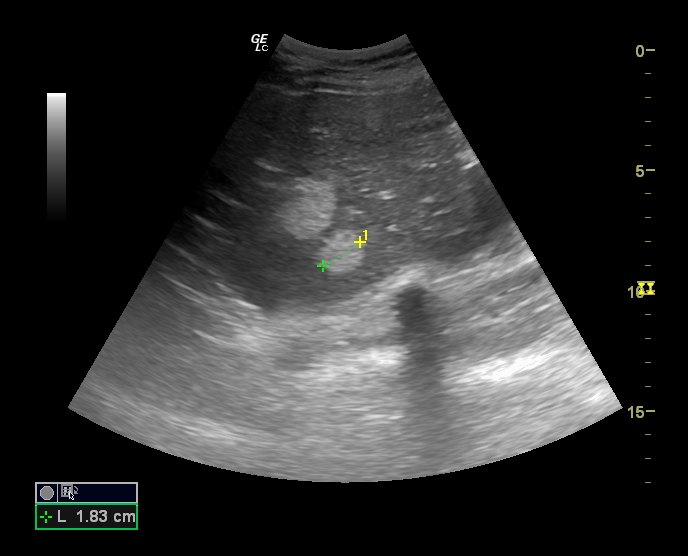

Hallazgos ecográficos

En la última ecografía realizada en febrero de 2023 presenta múltiples hemangiomas (lesiones hiperecogénicas), el de mayor tamaño en lóbulo caudado de 41 x 38 mm, segmento VIII dos, uno de 53 x 40 mm y otro de 17 mm, en segmento IV de 16 mm y en segmento VII de 9 mm.